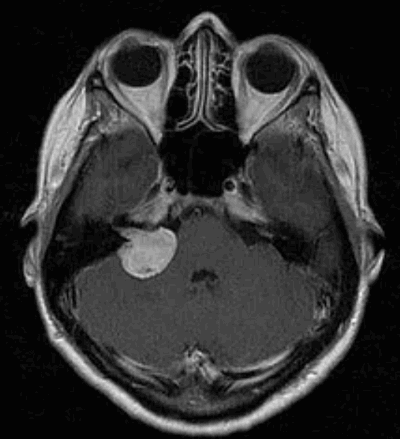

Шваннома височной кости на томограмме

Наиболее информативным методом выявления вестибулярных шванном является МРТ головного мозга с контрастным усилением в режиме Т1 и Т2. Это исследование позволяет определить размеры опухоли, наличие перитуморозного отека, наличие признаков окклюзионной гидроцефалии, которая может быть следствием сдавления опухолью IV желудочка. Кроме этого МРТ позволяет провести дифференциальную диагностику с другими опухолями схожей локализации (чаще с менингиомой задней грани пирамиды височной кости). Еще одним стандартом диагностики является КТ в костном режиме. Независимо от снижения слуха стандартом является проведение аппаратной аудиографии.

а) Вестибулярные шваномы (акустические невриномы) составляют около 10% среди причин односторонней сенсоневральной тугоухости и вестибулярной дисфункции неизвестной этиологии. Большинство опухолей возникает из вестибулярного нерва во внутреннем слуховом проходе. МРТ является методом выбора в оценке мостомозжечкового угла. Формат исследования зависит от клинической симптоматики.

Вестибулярная шваннома справа: компьютерная томографическая пневмоцистернограмма.

Воздух окаймляет выпуклость медиальной поверхности опухоли, вдающейся из внутреннего слухового прохода в прилегающую мостомозжечковую цистерну. Вестибулярная шваннома; МРТ: А. Быстрое спиновое эхо (FSE); Б. Т1 после контраста.

Опухоль хорошо видна в FSE изображении как заполняющая дефекты в яркой цереброспинальной жидкости (А).

Размер опухоли наиболее четко определяется при постконтрастном исследовании (Б). Шваннома лицевого нерва; МРТ.